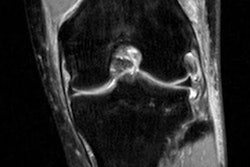

This MRI from InsideInjuries.com shows the location of a mensical tear. All images courtesy of Dr. Anand Lalaji.

"We always hear about these injuries, but we really have no idea what they look like," Lalaji said. "We can only associate to them by, 'Yes, I know that is a knee.' If I can give people a snapshot or a little snippet of what [an injury] looks like and what normal looks like, the next time they hear about that injury they automatically can visualize [it]. "

Just to be clear, the clinical images posted on the website are not of the athletes. If the pictures were the athletes' actual images, it would be an obvious HIPAA violation. In fact, InsideInjuries.com specifically states that the images are only examples of the injury the athlete incurred, based on media reports.